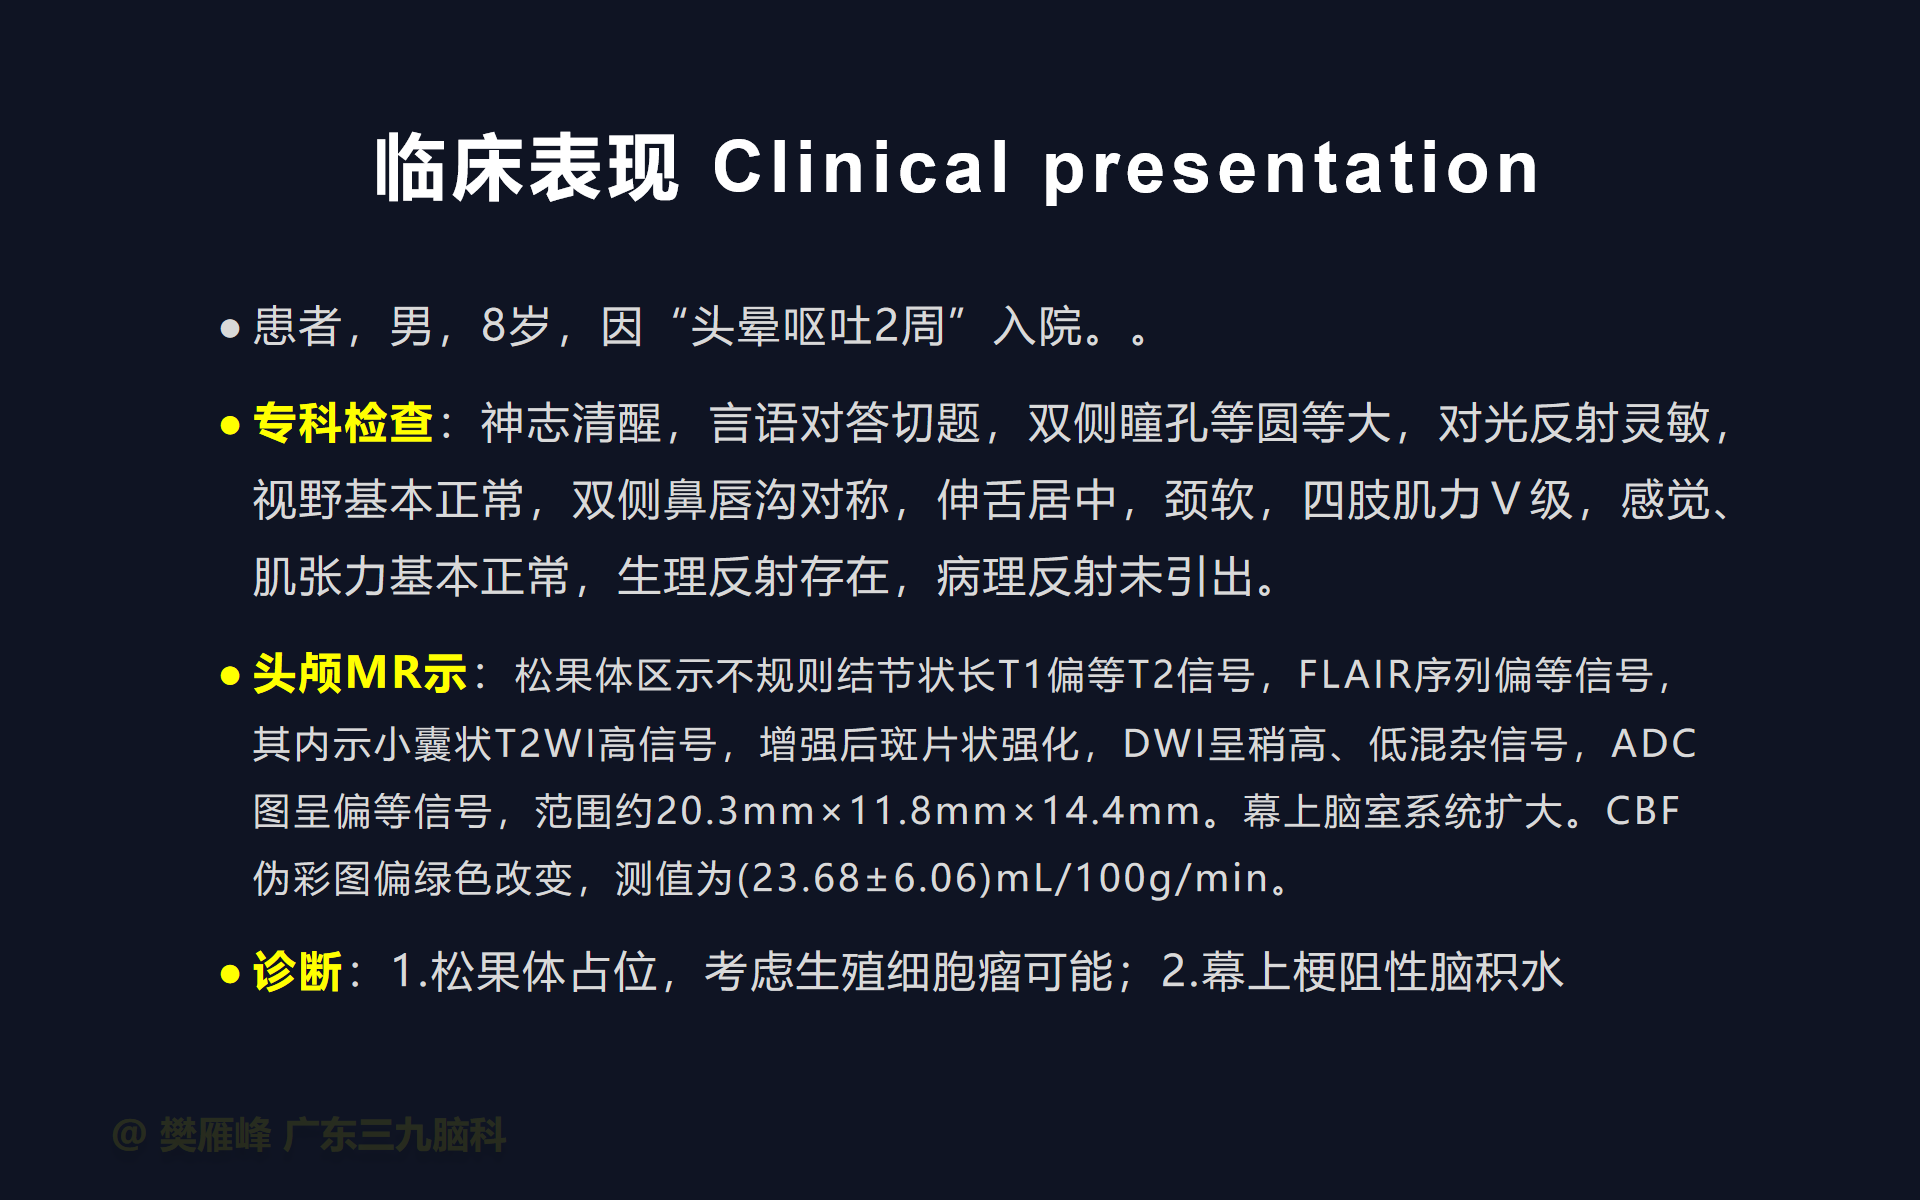

在这个二维手术视频中,展示了2例神经内镜下三脑室底造瘘+活检治疗三脑室后部肿瘤的方法。患者均为三脑室后部病变导致的梗阻性脑积水,病理结果1例为生殖细胞瘤,1例为淋巴瘤,在经过术后的放化疗病情均得到控制,生活质量满意。我们展示了安全的病变活检和第三脑室造瘘的技术要点,以最大限度减少术后继发脑积水和早期并发症。